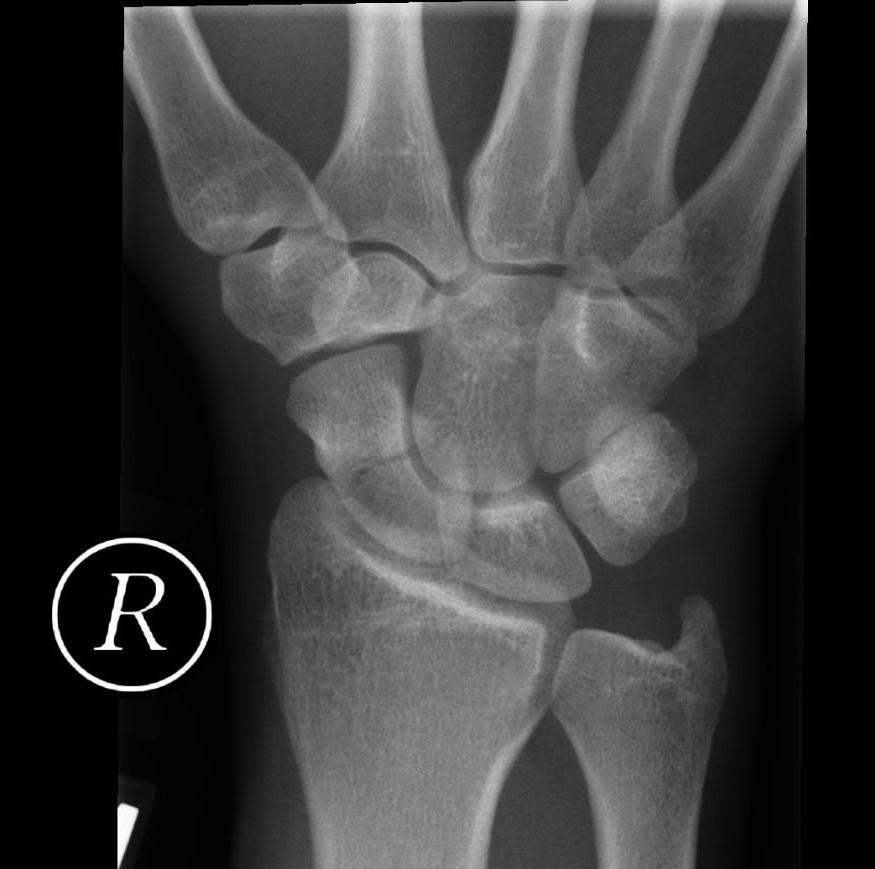

Radiograph of the wrist demonstrating a scaphoid bone fracture.